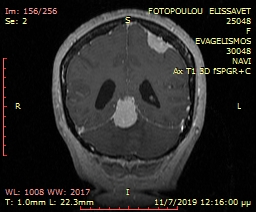

Επιδερμοειδής όγκος οπίσθιου βόθρου, σε γυναίκα 46 ετών, στην οποία προκαλούσε αφόρητο πόνο κεφαλής και προσώπου